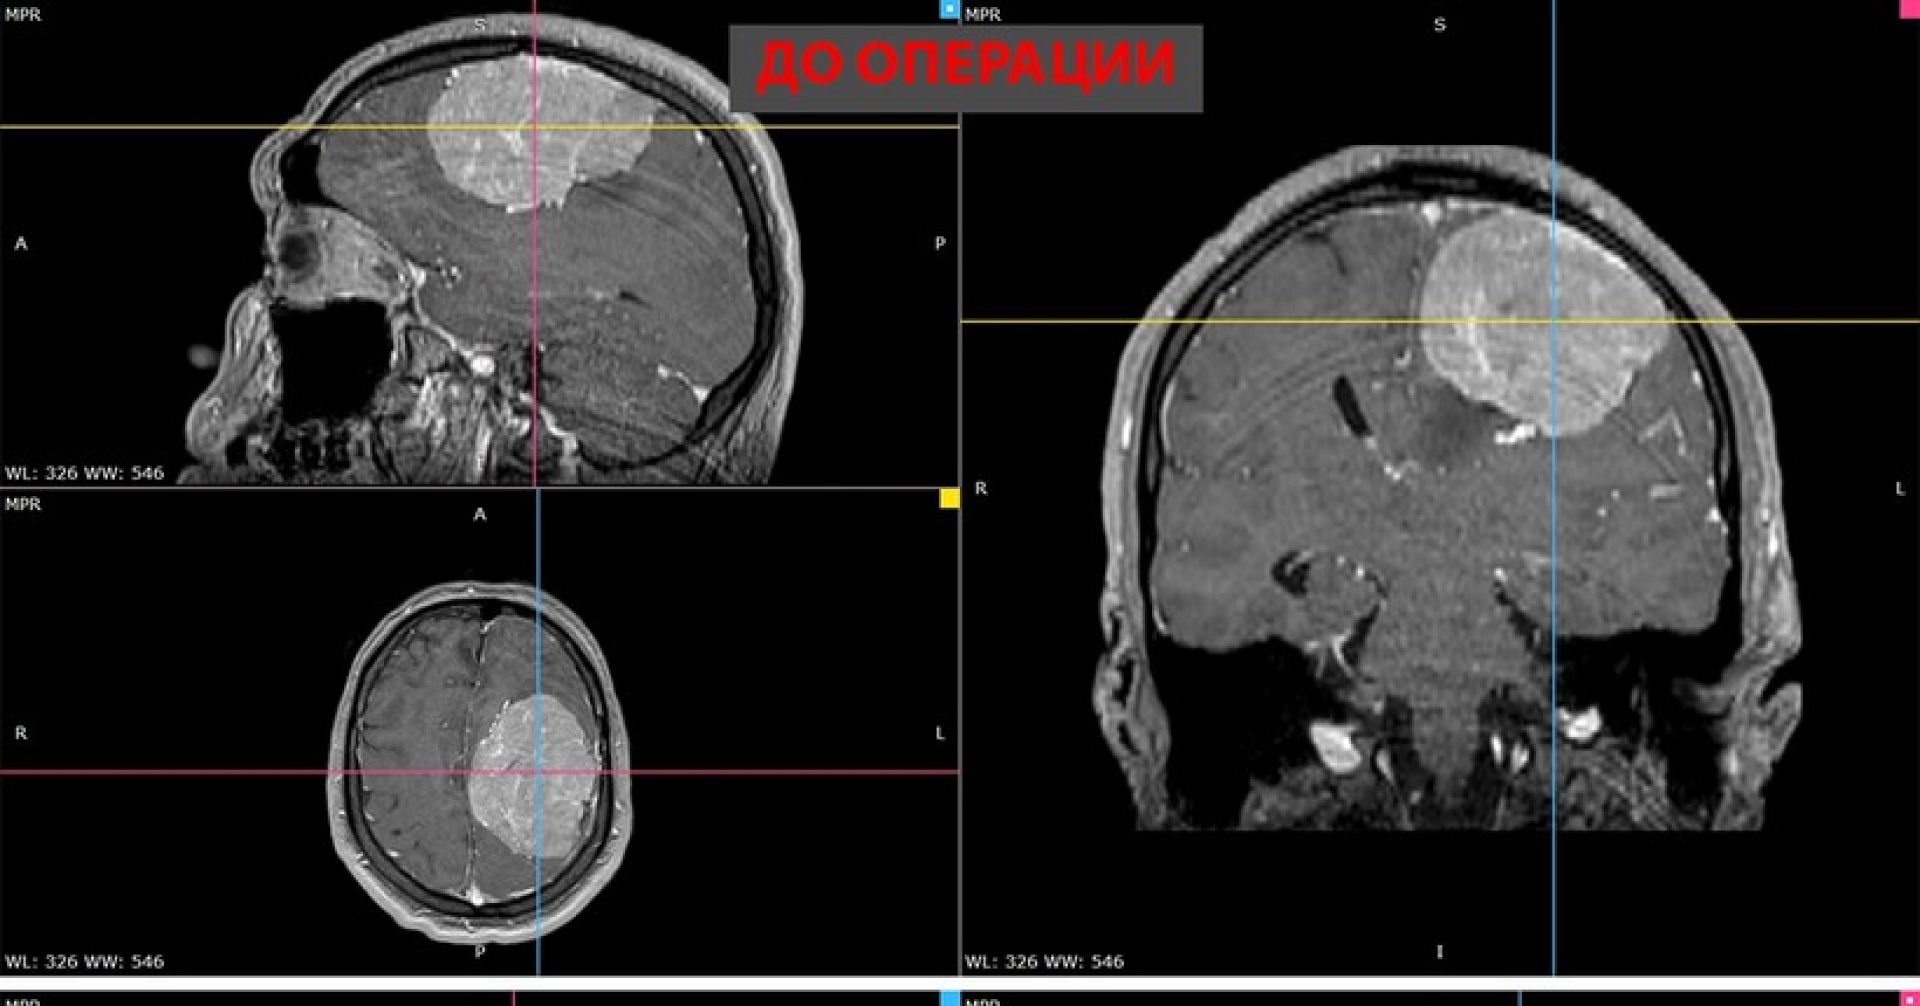

В ноябре прошлого года у 35-летнего мужчины появилась слабость в правой руке и затруднения речи. МРТ показала, что у него опухоль диаметром более восьми сантиметров в левом полушарии мозга. К концу года рука практически перестала работать, ходьба давалась пациенту с трудом. В январе, когда мужчина готовился к плановой операции, у него выявили тромбоэмболию лёгочной артерии. Хирурги временно отказались от вмешательства, боясь осложнений.

Фото: пресс-служба НМИЦ имени Мешалкина